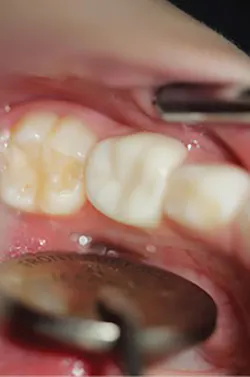

Cementation was then achieved as follows: Once satisfied with fit and occlusion, the prepared tooth was washed and dried but not desiccated. The NuSmile zirconia crown to be cemented was filled with cement (BioCem; NuSmile). Working time was approximately 60 seconds. The crown was set into the correct position. BioCem was photo cured with a tack cure of 10 seconds to the facial and 10 seconds to the palatal aspect. The cement was then cleaned interproximally using floss. Once all cement was removed, a final photo cure of 10 seconds to the facial and palatal was applied. One-month postoperative occlusal view and occlusion are pictured in Figures 4a and 4b.

Figures 4a and 4b: Final restoration